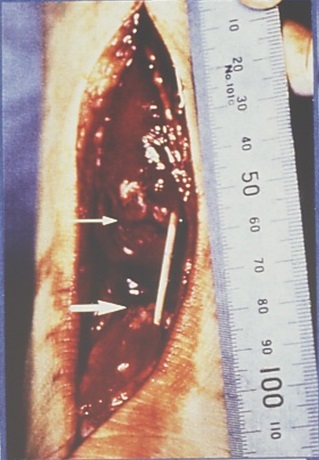

治療は手術療法と保存療法(非手術)に大別されます。基本的には治療期間に大差はなく、筆者は保存療法によるオリンピック代表選手の完全復帰例を経験しています。 手術療法:断裂したアキレス腱を直視下で確認しつつ(写真3)、縫合糸にて断裂部を縫合し、術後はギプスで固定を行います。ギプスの固定期間は手術法で4~6週(シーネ含む)、保存療法で6週を要します。ギプス固定後は約1ヶ月間装具を用いて歩行します。 保存療法:受傷時は断裂した腱の接近を目的として、足関節最大底屈位(50度以上)にして膝下からのギプス固定を行います(写真4)。荷重はフロアタッチ程度で、ギプス固定下でも下肢の屈伸運動は許可します。2週間経過した受傷後3週目で足関節約30度底屈位の固定に変更し、荷重は軽度の部分荷重とします。 受傷後5週目から足関節軽度底屈位で、ヒール付きギプス固定として全荷重歩行を行います。受傷7週より約1ヵ月間は短下肢装具を使用し、足関節の自動運動訓練を開始します。受傷11週目より装具をはずします。

写真3 手術時のアキレス腱断裂部(矢印)